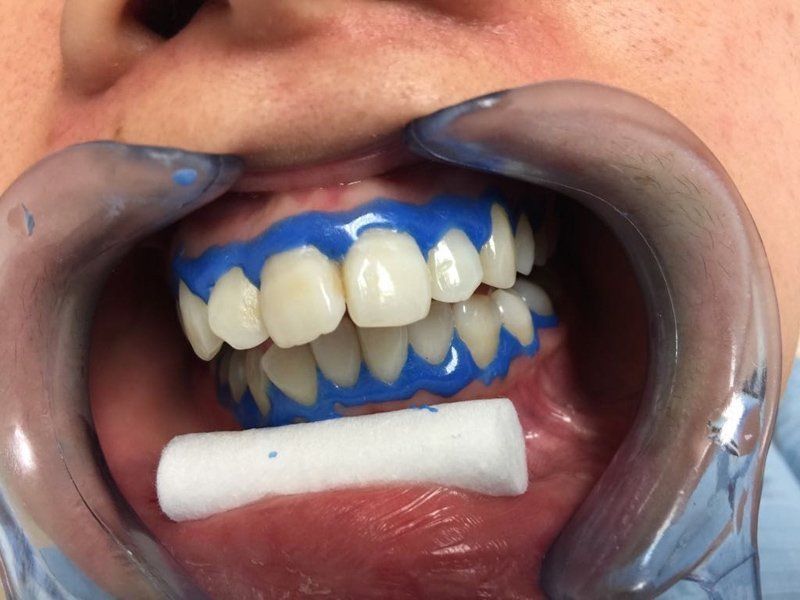

Sbiancamento con led

Prima e dopo una sola seduta d’igiene orale professionale in paziente maschile fumatore, il risultato può essere ulteriormente migliorato con un trattamento di sbiancamento.